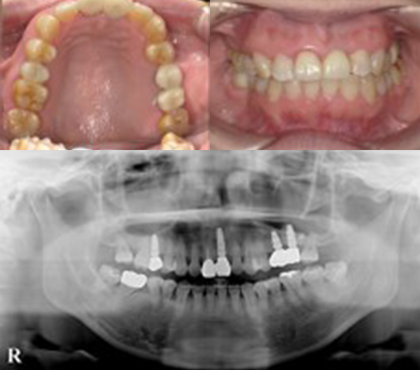

症例

奥歯は欠損放置による骨量不足のため骨増生を行い、前歯は破折歯をジルコニアセラミックとインプラントで補綴しました。前歯4本はオールセラミックにて修復しています。

修復前

修復後

| 治療費用 |

インプラント 1本 385,000円×4本 オールセラミック 1本 130,000 円×1本 骨増生 55,000円 |

|---|---|

| 治療のリスクについて | 骨増生の際には、一時的に腫れを伴うことがあります。当院では、麻酔専門医による静脈内鎮静法を併用し、腫れを抑える薬剤を適切に投与することで、患者様のご負担を軽減できるよう努めております。 |